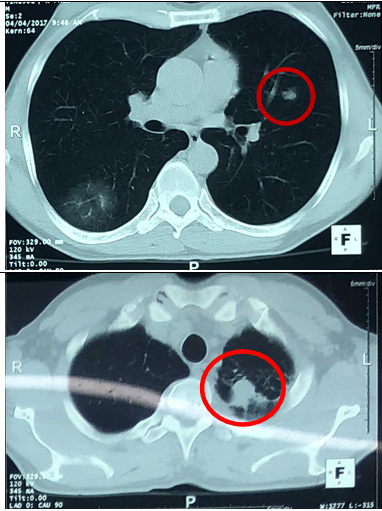

-   Cắt lớp vi tính lồng ngực: U thùy dưới phổi phải kích thước 56x81mm, ngấm thuốc sau tiêm. Khối mờ đỉnh phổi trái kích thước 28mm, nốt mờ nhỏ phân thùy lưỡi phổi trái.

Hình 1: Hình ảnh chụp cắt lớp vi tình lồng ngực

Trước điều trị: U phổi phải kích thước 56x81mm

Sau điều trị: U phổi phải kích thước 35x40mm

Trước điều trị: Khối mờ đỉnh phổi trái kích thước 28mm, nốt mờ thùy dưới phổi trái.

Sau điều trị: Khối mờ đỉnh phổi trái là dải xơ hóa, nốt mờ nhỏ thùy dưới phổi trái không còn.